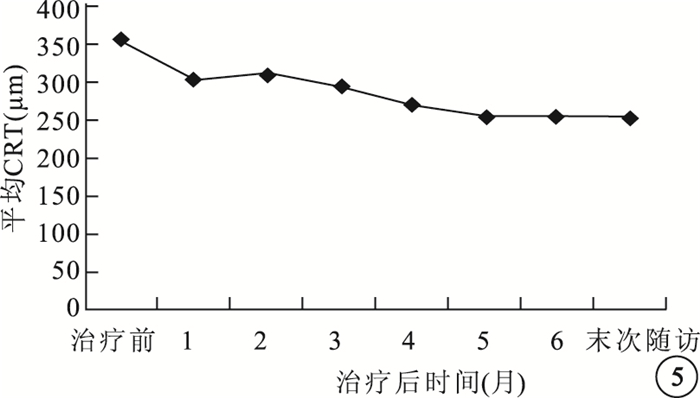

治療后1、3、6個月及末次隨訪時,患眼平均CRT分別為(284.25±66.12)、(295.05±104.17)、(256.00±64.06)、(255.60±55.43)μm,較治療前分別降低了(91.15±122.14)、(80.35±95.01)、(119.40±153.83)、(119.80±155.83)μm,差異均有統計學意義(t=3.34、3.78、3.47、3.44,P<0.05)(圖 5)。

圖5

患眼平均CRT變化趨勢

圖5

患眼平均CRT變化趨勢

治療后1、3、6個月及末次隨訪時,患眼平均CRT分別為(284.25±66.12)、(295.05±104.17)、(256.00±64.06)、(255.60±55.43)μm,較治療前分別降低了(91.15±122.14)、(80.35±95.01)、(119.40±153.83)、(119.80±155.83)μm,差異均有統計學意義(t=3.34、3.78、3.47、3.44,P<0.05)(圖 5)。

圖5

患眼平均CRT變化趨勢

圖5

患眼平均CRT變化趨勢